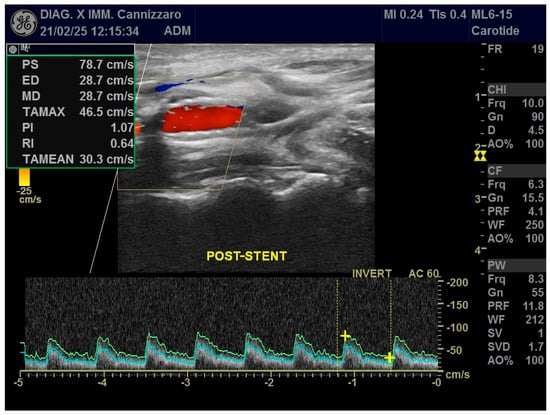

The procedure is performed in the angiographic suite, under mild sedation to monitor the neurological status of the patient, by arterial vascular access, usually femoral. With the wire–catheter system, the common carotid artery (CCA) of the pathological side is selectively catheterized and a diagnostic angiography is performed to identify the stenosed area (Figure 3). The stenosis carotid tract is crossed through the wire–catheter system, and only after the placement of a neuroprotection device in the ICA, a balloon angioplasty is performed to compress the atheromatic lesion and restore the original luminal vessel diameter. Regarding neuroprotection, today we have two classes of embolic protection devices available: a coaxial umbrella-like filter positioned in the distal ICA (Figure 4) or hemodynamic balloon block systems with reversal flow that can be placed either proximally or distally to the carotid stenosis with overlapping results in reducing the distal embolic phenomena risk but with a higher rate of periprocedural vasospasm in the case of a distal umbrella-like filter [53]. At this point, it is necessary to inject 1 mg of atropine to avoid vasospasm before releasing a permanent endovascular stent. We have three types of endovascular stents such as open-cell, closed-cell, or double-layer (Figure 5). Open-cell stents were worse than closed-cell due to the higher degree of plaque protrusion and the procoagulant state induced by the stent that can trigger embolic phenomena, recording a higher rate of stroke or restenosis at 30 days. The double-layer stents are still in the process of approval by the FDA although they have shown in some clinical trials strongly encouraging results with a risk of adverse events at 30 days <2% [54].

Figure 5. Final DSA control, in a patient with significant (>50%) stenosis of the ICA who has been treated by positioning a closed-cell stent (Boston Scientific Wallstent, 8 × 30 mm, 300 Boston Scientific Way Marlborough, MA 01752-1234) dilated with a balloon catheter (Ultraverse PTA dilatation catheter 6 × 20 mm, Becton, Dickinson and Company’s, 1 Becton Drive, Franklin Lakes, New Jersey 07417, USA).